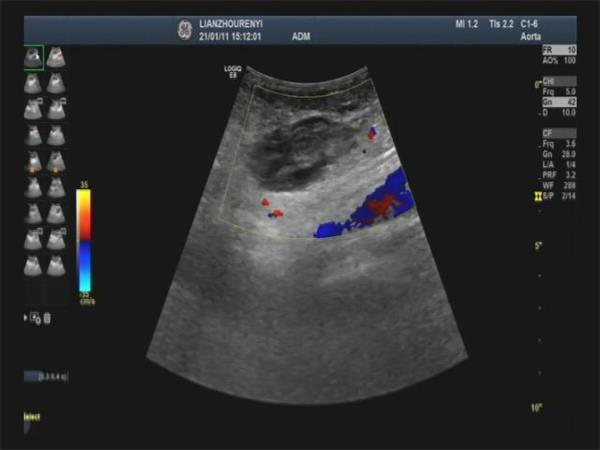

(术前超声见瘤体内可探及红蓝交替的血流信号)

在超声引导下,穿刺针至瘤腔远端,缓慢注射稀释凝血酶,注射后彩超显示瘤腔内血流信号逐渐消失,完成凝固治疗。术后复查患者疼痛缓解,无并发症发生,见漏口已完全闭塞,患者术中术后生命体征平稳。